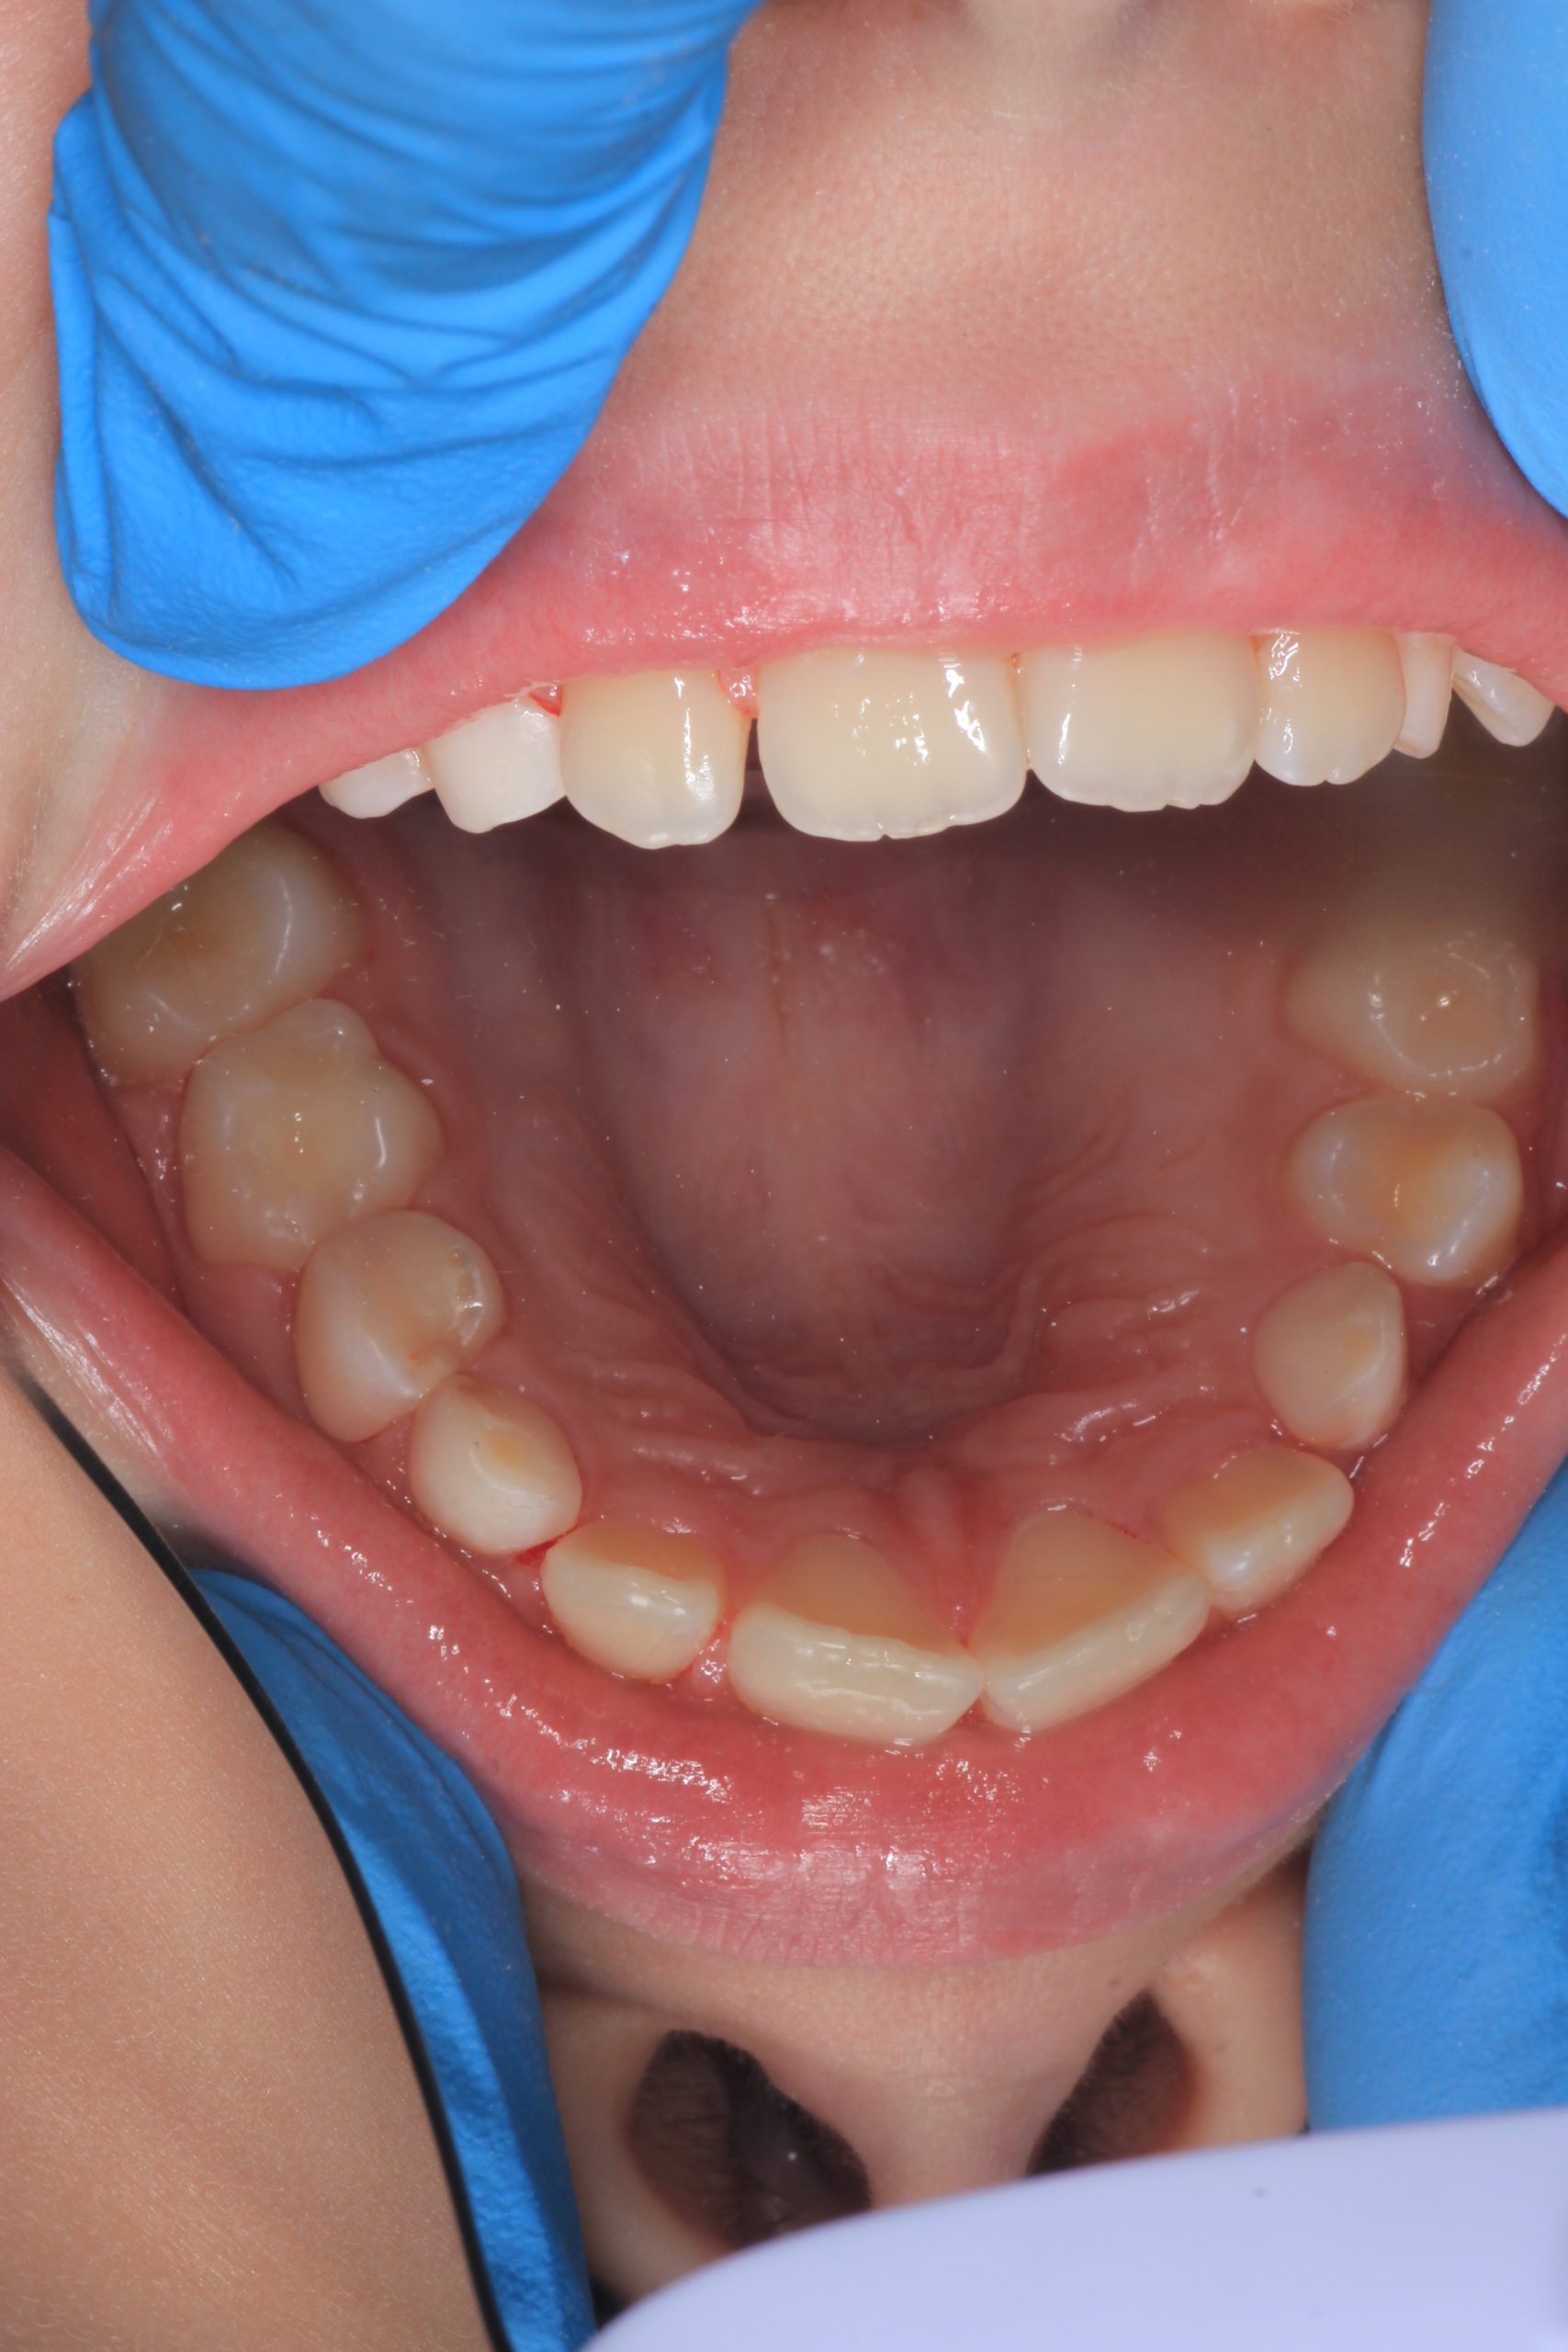

- Detailed Examination

We examine the condition of teeth, gums, and bite. - Plaque Disclosure with Special Indicators

Together with your child, we practice brushing techniques, correct mistakes, and provide personalized recommendations. We advise whether to use manual or electric brushes, floss, interdental brushes, or remineralizing gels. - Plaque Removal with AIRFLOW Prophylaxis Master (EMS, Switzerland)